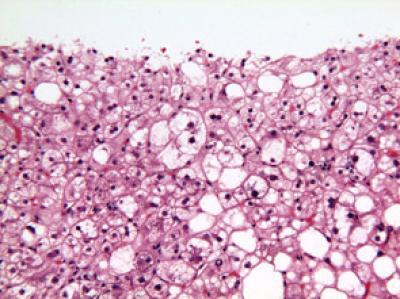

The second shows nonalcoholic steatohepatitis (NASH), a more serious condition with potential to progress to cirrhosis.

(Photo Credit: Elizabeth Brunt, M.D., of Washington University in Saint Louis.)